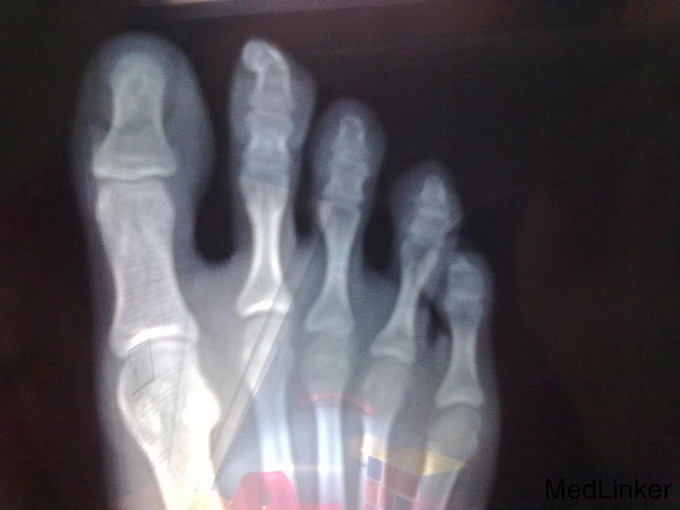

查体:皮肤科情况 :右足第2趾甲下可见一1cm× 0.8cm×1cm大小结节,表面角化明显,有触痛。辅助检查:血尿便常规、肝肾功能、电解质均未见明显异常。残留趾甲真菌镜检及培养阴性。足部 X 线检查 :右侧第2远节趾骨末端见骨性密度新生物影.

诊断:甲下外生性骨疣。 治疗:手术切除甲下外生骨疣,术后伤口愈合良好。术后组织病理示:真皮内成熟骨组织,间质中纤维组织增生。